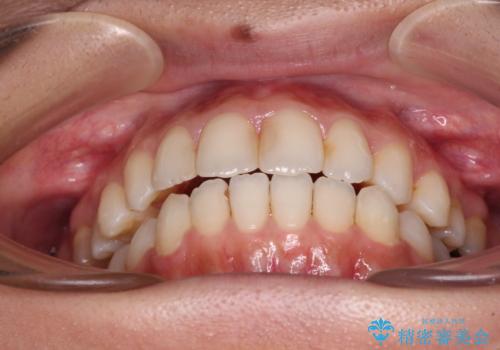

オープンバイトによる見た目を治したい インビザラインでの矯正治療

- オープンバイトのため、話しているときの見た目が気になるとのことで来院された患者様です。

下顎骨は左側にシフトしており、咬み合ったときには奥歯と前歯の一部しか接触していない状態でした。

骨格的な左右差は歯列矯正は改善できないため、上下歯列が全体的に接触することをゴールとしてインビザラインにて矯正治療を行うこととしました。

前歯のデコボコの解消と並行して上下の奥歯を圧下させるようにすることで、前歯を接触させるように計画しました。

上下の隙間に舌が入り込むことがオープンバイトの原因であったため、舌の筋肉のトレーニングも並行して行い、後戻りの抑制を図りました。